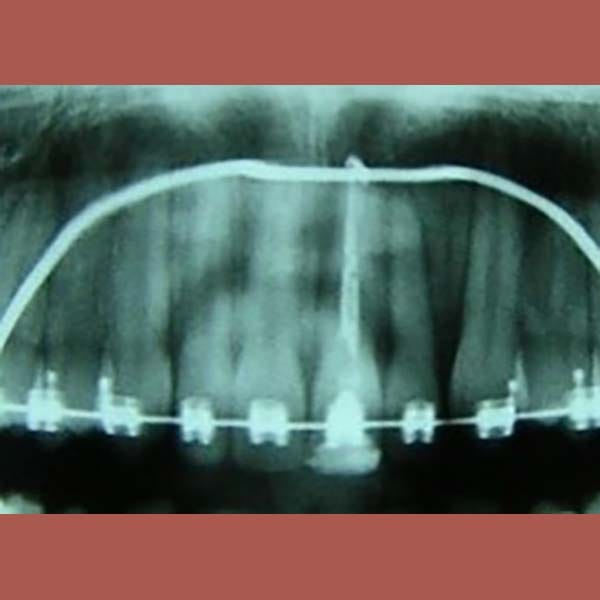

يعتبر انطمار الأنياب العلوية في العظم من الحالات التي تتطلب تدخلاً تقويمياً دقيقاً. بصفتي أخصائي تقويم أسنان في العين، أعمل على خطط علاجية تضمن إنزال هذه الأسنان بأمان. هذه الحالة توضح خطوات علاج الناب المنطمر بالتقويم، من فتح المسافة إلى جره لمكانه الصحيح.

بعد التشخيص الدقيق، وضع الدكتور خالد الكاتب خطة علاجية من مرحلتين باستخدام تقويم الأسنان:

كما تظهر الصور، تم إنزال الناب المنطمر بنجاح ورصفه بشكل مثالي مع بقية الأسنان. النتيجة هي ابتسامة كاملة وصحية، واستعادة سن مهم جداً لوظيفة الفم وجمال الابتسامة.